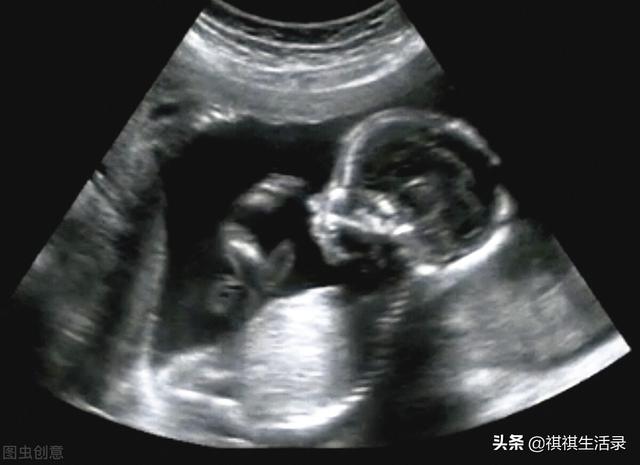

而且,如今的医疗水平发展非常迅速。当宝宝在妈妈肚子里的时候,父母可以通过检查看到孩子的大致样子。

家里有孕妇的人一般都知道,做四维彩超的时候,大概是怀孕二十四周,宝宝要四十周左右才会出生。

所以做四维工作的时候距离宝宝出生还有一段时间。这个阶段宝宝刚刚成型,五官还没有发育好。而且,做四维工作的目的不是为了观察胎儿的外貌。

是为了健康胎儿的畸形和自身胎儿的大脑和四肢的发育。所以,准父母看到四维图不要惊讶。这只是胎儿最初发育的样子,并不是宝宝最后的样子。

医院里的四维机并不能真正通过母亲的胃给子宫里的婴儿拍照,而是可以通过声波的反馈来映射画面。

所以在这个过程中,孕妇子宫内的羊水等物质会给作图带来干扰,导致画面不太准确,肯定或多或少会有误差。